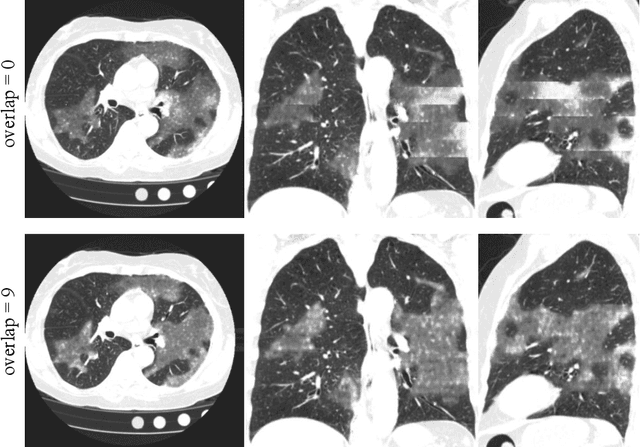

Abstract:The Coronavirus Disease (COVID-19) has affected 1.8 million people and resulted in more than 110,000 deaths as of April 12, 2020. Several studies have shown that tomographic patterns seen on chest Computed Tomography (CT), such as ground-glass opacities, consolidations, and crazy paving pattern, are correlated with the disease severity and progression. CT imaging can thus emerge as an important modality for the management of COVID-19 patients. AI-based solutions can be used to support CT based quantitative reporting and make reading efficient and reproducible if quantitative biomarkers, such as the Percentage of Opacity (PO), can be automatically computed. However, COVID-19 has posed unique challenges to the development of AI, specifically concerning the availability of appropriate image data and annotations at scale. In this paper, we propose to use synthetic datasets to augment an existing COVID-19 database to tackle these challenges. We train a Generative Adversarial Network (GAN) to inpaint COVID-19 related tomographic patterns on chest CTs from patients without infectious diseases. Additionally, we leverage location priors derived from manually labeled COVID-19 chest CTs patients to generate appropriate abnormality distributions. Synthetic data are used to improve both lung segmentation and segmentation of COVID-19 patterns by adding 20% of synthetic data to the real COVID-19 training data. We collected 2143 chest CTs, containing 327 COVID-19 positive cases, acquired from 12 sites across 7 countries. By testing on 100 COVID-19 positive and 100 control cases, we show that synthetic data can help improve both lung segmentation (+6.02% lesion inclusion rate) and abnormality segmentation (+2.78% dice coefficient), leading to an overall more accurate PO computation (+2.82% Pearson coefficient).